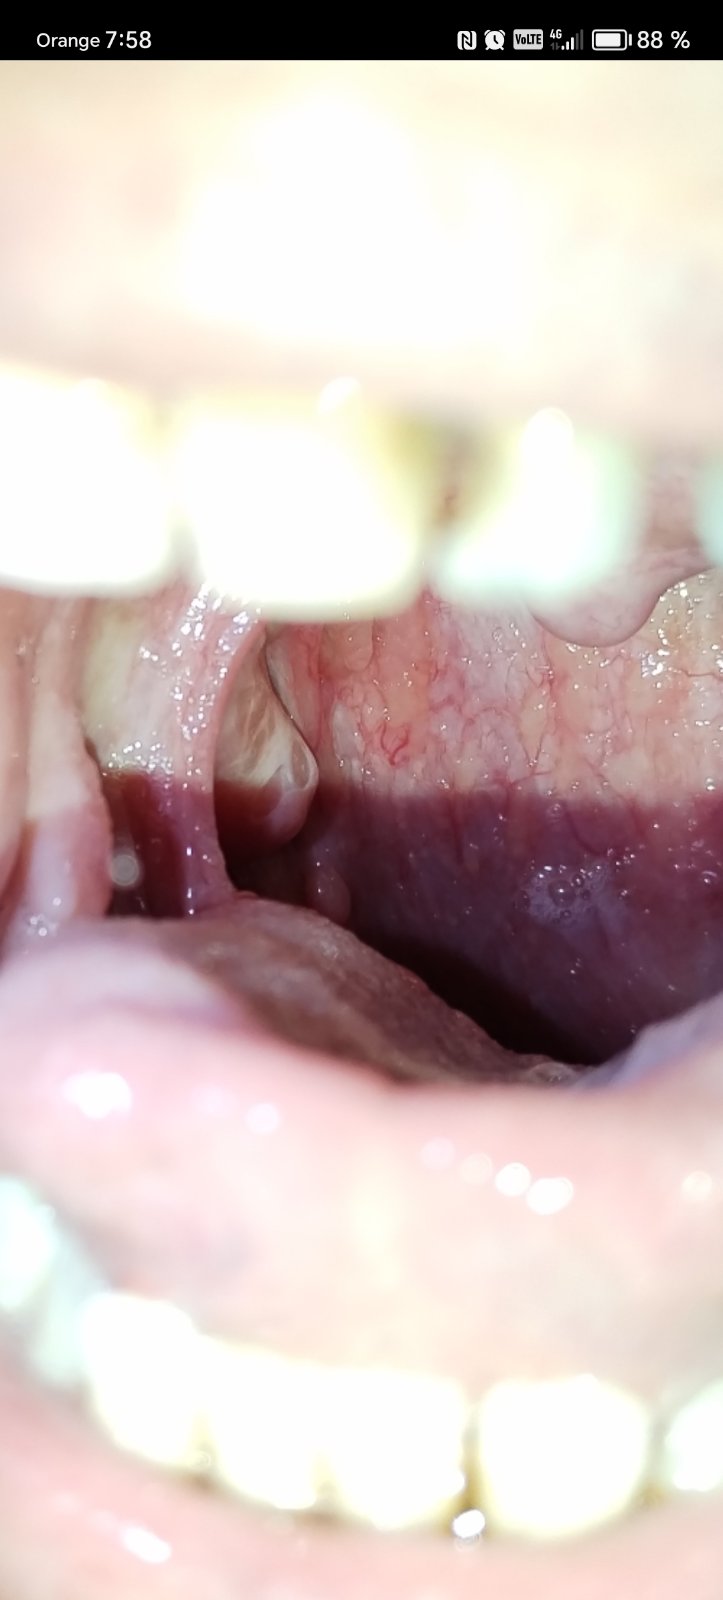

Mali ste uz skusenost hrckov dnuka v hrdle pri mandli?

@hajni1988 Boli ste s tým niekde? Mám niečo podobné.. tiež nvm

@evelinhb ja mam cistu raz sa stiahne po čase sa zas náplní ale velkost nemeni